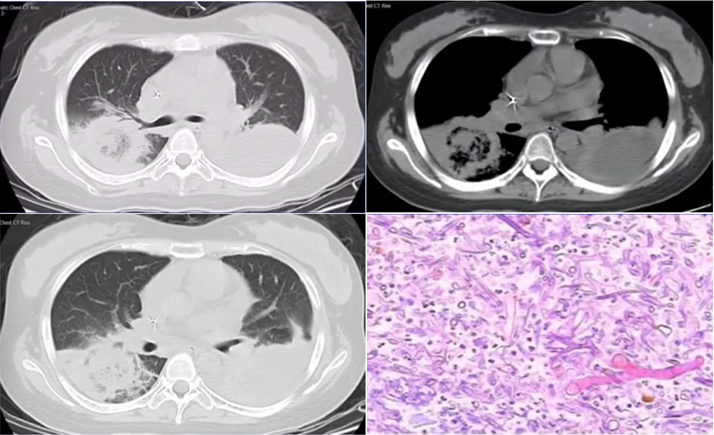

下图为一肿块,周围有晕征,中间有小气泡,增强扫描可见大片坏死,没有强化(图19),这种特征非常像曲霉感染,但最终穿刺病理证实为毛霉感染。其破坏范围更广。临床上,在诊断不清的情况下,一定要做增强扫描,能够帮助确定组织强化的程度。患者出现了胸腔积液,其中的小气泡更大,这是毛霉的特征。

图片

图19  毛霉感染

毛霉感染患者胸部CT可见反晕征,有胸腔积液,说明病变侵犯力非常强。其次,病变中的分隔粗大,其中的小气胞分布范围广。另外,病变中没有看到气液平面。但是由于病灶的破坏力更强更快,毛霉的生长跟不上,坏死物固定相对较弱,所以其病变破坏更多向外扩张,对血管的破坏性更大,因此我们看到很多低密度影。这是毛霉的特征。毛霉破坏组织后产生一些组织残留,因此CT上可见很多分隔(图20,图21)

图20  毛霉感染—反晕征,胸腔积液,分隔粗大

图21  毛霉感染—病变范围广、反晕征、胸腔积液